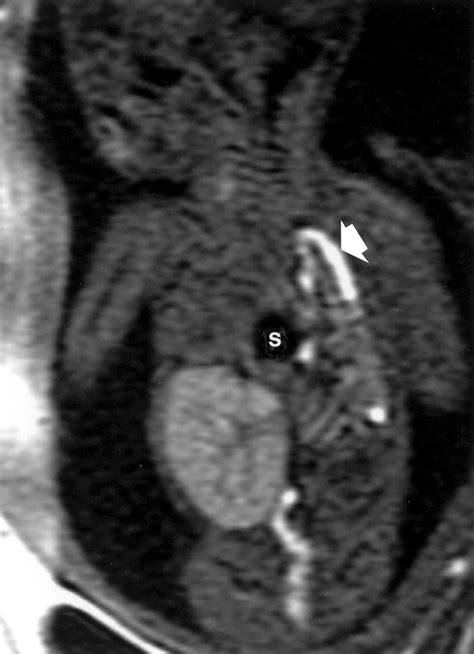

In many modern medical settings, CDH is often identified before birth during routine prenatal ultrasounds. If an anomaly is suspected, doctors may utilize fetal MRI or advanced echocardiograms to assess the severity of lung development and heart positioning.

To fully grasp what is CDH, one must understand how it physically alters a newborn's anatomy. The diaphragm is essential for normal breathing. When a hole exists in this muscle, the vacuum pressure changes within the thoracic cavity. As the abdominal organs migrate into the chest, they compress the developing lungs, hindering the branching of the airways and the development of blood vessels.

The severity of CDH is largely determined by the timing of the defect during gestation and the specific organs that migrate into the chest. In many cases, the heart may also be pushed out of its normal position, which can further impact circulatory function at birth. This combination of underdeveloped lungs and potential circulatory strain is why babies born with CDH require specialized neonatal care immediately upon delivery.